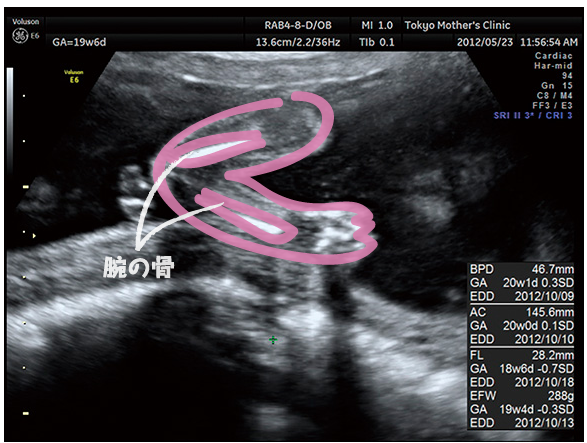

妊娠4ヶ月のエコー写真の様子 妊娠4ヶ月になると顔の形や腕、脚などが見えるようになり体形も赤ちゃんのようになってきました。 赤ちゃんの全身がエコーに写るのは妊娠4ヶ月~5ヶ月頃までなので上手に写ってくれるといいですね。 妊娠13週0日 妊娠中期. 妊娠・出産 胎児の様子 エコー(超音波検査) 妊娠中期 妊娠5ヶ月 妊娠16週 30歳~34歳 女性 2人目以降 今回3度目の妊娠。 全て同じ産院で、4Dエコーを見せてくれるところでした。.